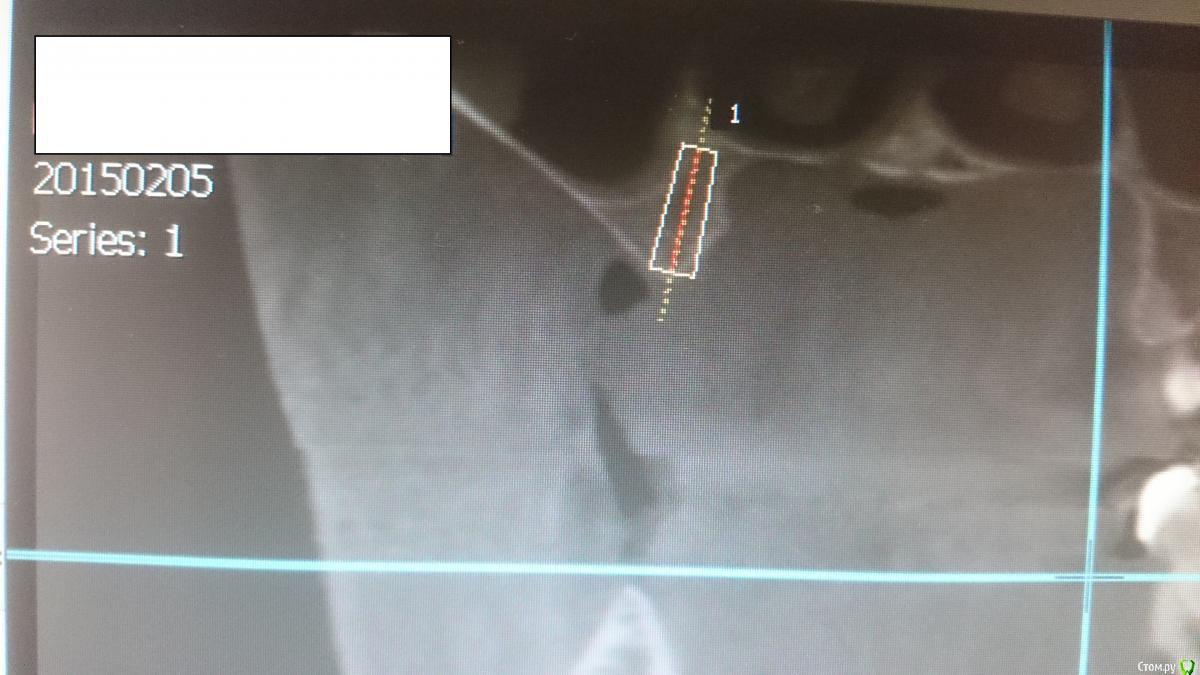

JIM Опубликовано 29 апреля, 2015 Поделиться Опубликовано 29 апреля, 2015 Ставить ли имплантат как на снимке, либо строго вертикально с синусом? (область 16 зуба) Ссылка на комментарий

JIM Опубликовано 29 апреля, 2015 Автор Поделиться Опубликовано 29 апреля, 2015 подумайте про ортопедию... угол примерно в 10 градусов мне не кажется большой проблемой... Ссылка на комментарий

aloshak Опубликовано 29 апреля, 2015 Поделиться Опубликовано 29 апреля, 2015 Только кости по ширине маловато..плюсуюсь Ссылка на комментарий

Bier Опубликовано 29 апреля, 2015 Поделиться Опубликовано 29 апреля, 2015 3.5 встанет туда без пластик 2 Ссылка на комментарий

lonely_jack Опубликовано 29 апреля, 2015 Поделиться Опубликовано 29 апреля, 2015 если четко, как на снимке, поставить, думаю, проблем не будет...проблемка только в таком четком позиционировании при операции))) я за! выложите плз кт после))) Ссылка на комментарий

Tabula Rasa Опубликовано 7 мая, 2015 Поделиться Опубликовано 7 мая, 2015 (изменено) 1.6 - отсутствует первый моляр,мощный зуб,несущий значимость в биомеханике..Нужна нормальная ширина и высота,чтобы поставить адекватного диаметра имплант.Сделать одномоментно с синусом + по ширине от синуса натянуть мембрану на гребень на пины-можно попробовать,но риск высокий.Иначе-синус+гребень по ширине -> ждем и имплант. Изменено 7 мая, 2015 пользователем Tabula Rasa Ссылка на комментарий